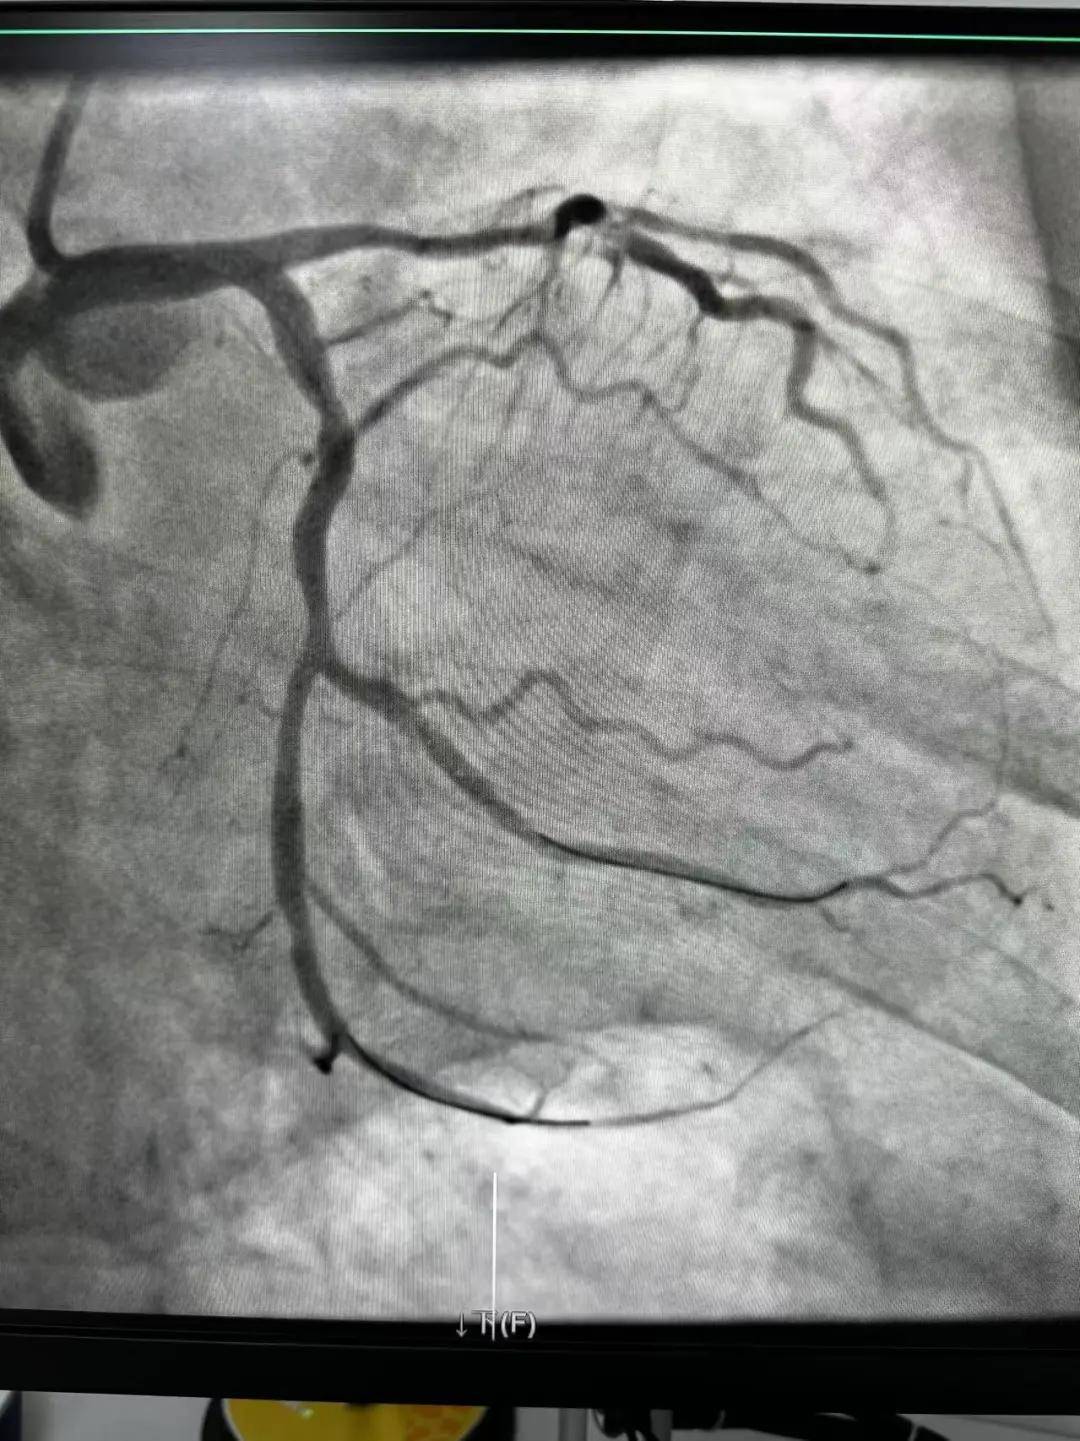

今天最后一臺手術(shù),是一個嚴重三支病變的病人,患者張大爺,71歲,以“突發(fā)胸悶胸痛3小時”為主訴入院。經(jīng)心電圖檢查后示室上性心動過速,以“冠心病、心絞痛、心律失?!睘樵\斷收住入心內(nèi)科。心內(nèi)科團隊通過審慎評估,決定給予患者冠狀動脈造影術(shù)及冠狀動脈內(nèi)支架置入術(shù)。

穿刺、造影、放支架……兩個手術(shù)間各個環(huán)節(jié)緊張卻有序地進行著!在心內(nèi)科團隊精準、默契的配合下,兩臺手術(shù)順利完成! 兩名患者的快速、同時、成功救治,得益于殷都區(qū)人民醫(yī)院醫(yī)務(wù)人員快速的應(yīng)急能力、過硬的急救技能,同時更得益于導(dǎo)管室同開臺,保障了救治的迅速有效。